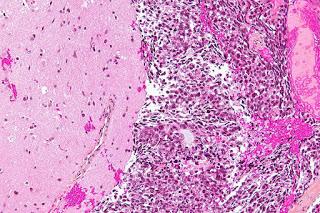

Micrographie à fort grossissement de métastases intracrâniennes (cerveau). Le tissu cérébral normal est localisé sur la gauche du cliché; la tumeur est visible sur la droite. La nette démarcation entre le tissu normal et le tissu tumoral est typique de métastases cérébrales.

Source: https://commons.wikimedia.org/wiki/File:Brain_metastasis_-_high_mag.jpg